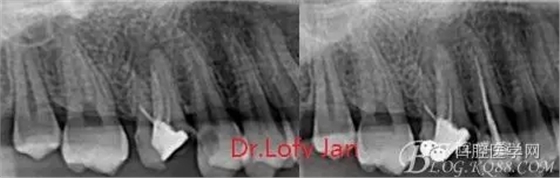

曲面斷層片在未試尖根管治療中的病例整理

前言:自己做的一些曲面斷層片在未試尖根管治療中的病例整理,發(fā)現(xiàn)問題很多包括自身的,技術(shù)的,還有設(shè)備的問題,予以總結(jié)整理并期待進(jìn)一步提高。

病例分析:曲面斷層片在x線輔助診斷與檢查中目前大多數(shù)文獻(xiàn)和著作都建議只能作為初診拍片檢查手段,不能作為終末疾病的確診與手術(shù)療效的評(píng)價(jià)指標(biāo),臨床大部分中小型門診都因?yàn)樵O(shè)備不齊全導(dǎo)致信息偏差很大。